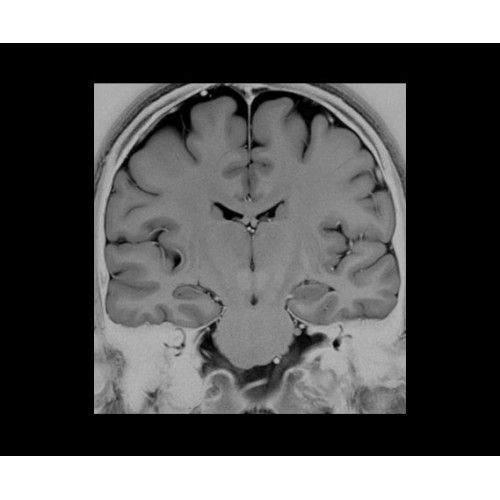

SIGNA PET/MR 3.0T — это гибридная система, в которой совмещаются две принципиально разные технологии — магнитно-резонансную томографию (МРТ) и позитронно-эмиссионную томографию (ПЭТ). Система отличающийся высокой чувствительностью и эффективностью и предназначена для диагностики в области онкологии, неврологии, кардио-васкулярных исследований, исследований воспалительных процессов.

Компания GE Healthcare представляет революционную, полностью интегрированную систему SIGNA PET/MR1, в которой сочетаются времяпролетная технология (TOF) и возможности напряженности магнитного поля 3.0 Тл. Мы поможем вам поднять исследования на более высокий уровень. SIGNA PET/MR позволяет достичь впечатляющей точности и скорости исследований, а благодаря новейшей технологии реконструкции Q.Clear2 качество изображений улучшается в два раза. Кроме того, в систему включен полный набор клинических приложений и гибких катушек для проведения любых видов исследования, открывая для вас возможности визуализации, о которых вы даже не догадывались.

Стандартный пакет приложений SIGNA Works позволит вам достичь желаемых результатов в клинической практике благодаря набору высокоэффективных средств визуализации. Программные приложения, входящие в состав данных клинических пакетов, включают широкий спектр контрастов, функции обработки 2D- и 3D-данных, а также возможность коррекции артефактов движения. SIGNA Works предоставляет набор инструментов, необходимых для проведения эффективного клинического исследования.